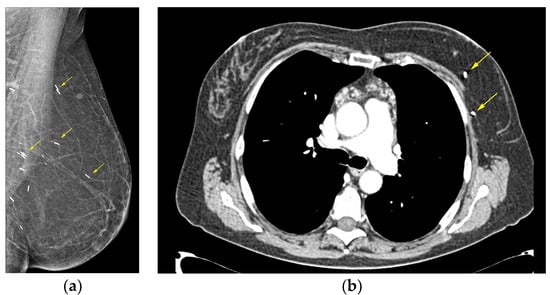

- Kerridge, W.D.; Kryvenko, O.N.; Thompson, A.; Shah, B.A. Fat Necrosis of the Breast: A Pictorial Review of the Mammographic, Ultrasound, CT, and MRI Findings with Histopathologic Correlation. Radiol. Res. Pract. 2015, 2015, 613139. [Google Scholar] [CrossRef] [PubMed]

- Taboada, J.L.; Stephens, T.W.; Krishnamurthy, S.; Brandt, K.R.; Whitman, G.J. The many faces of fat necrosis in the breast. Am. J. Roentgenol. 2009, 192, 815–825. [Google Scholar] [CrossRef] [PubMed]

- Daly, C.P.; Jaeger, B.; Sill, D.S. Variable appearances of fat necrosis on breast MRI. Am. J. Roentgenol. 2008, 191, 1374–1380. [Google Scholar] [CrossRef] [PubMed]

- Trimboli, R.M.; Carbonaro, L.A.; Cartia, F.; Di Leo, G.; Sardanelli, F. MRI of fat necrosis of the breast: The “black hole” sign at short tau inversion recovery. Eur. J. Radiol. 2012, 81, e573–e579. [Google Scholar] [CrossRef] [PubMed]